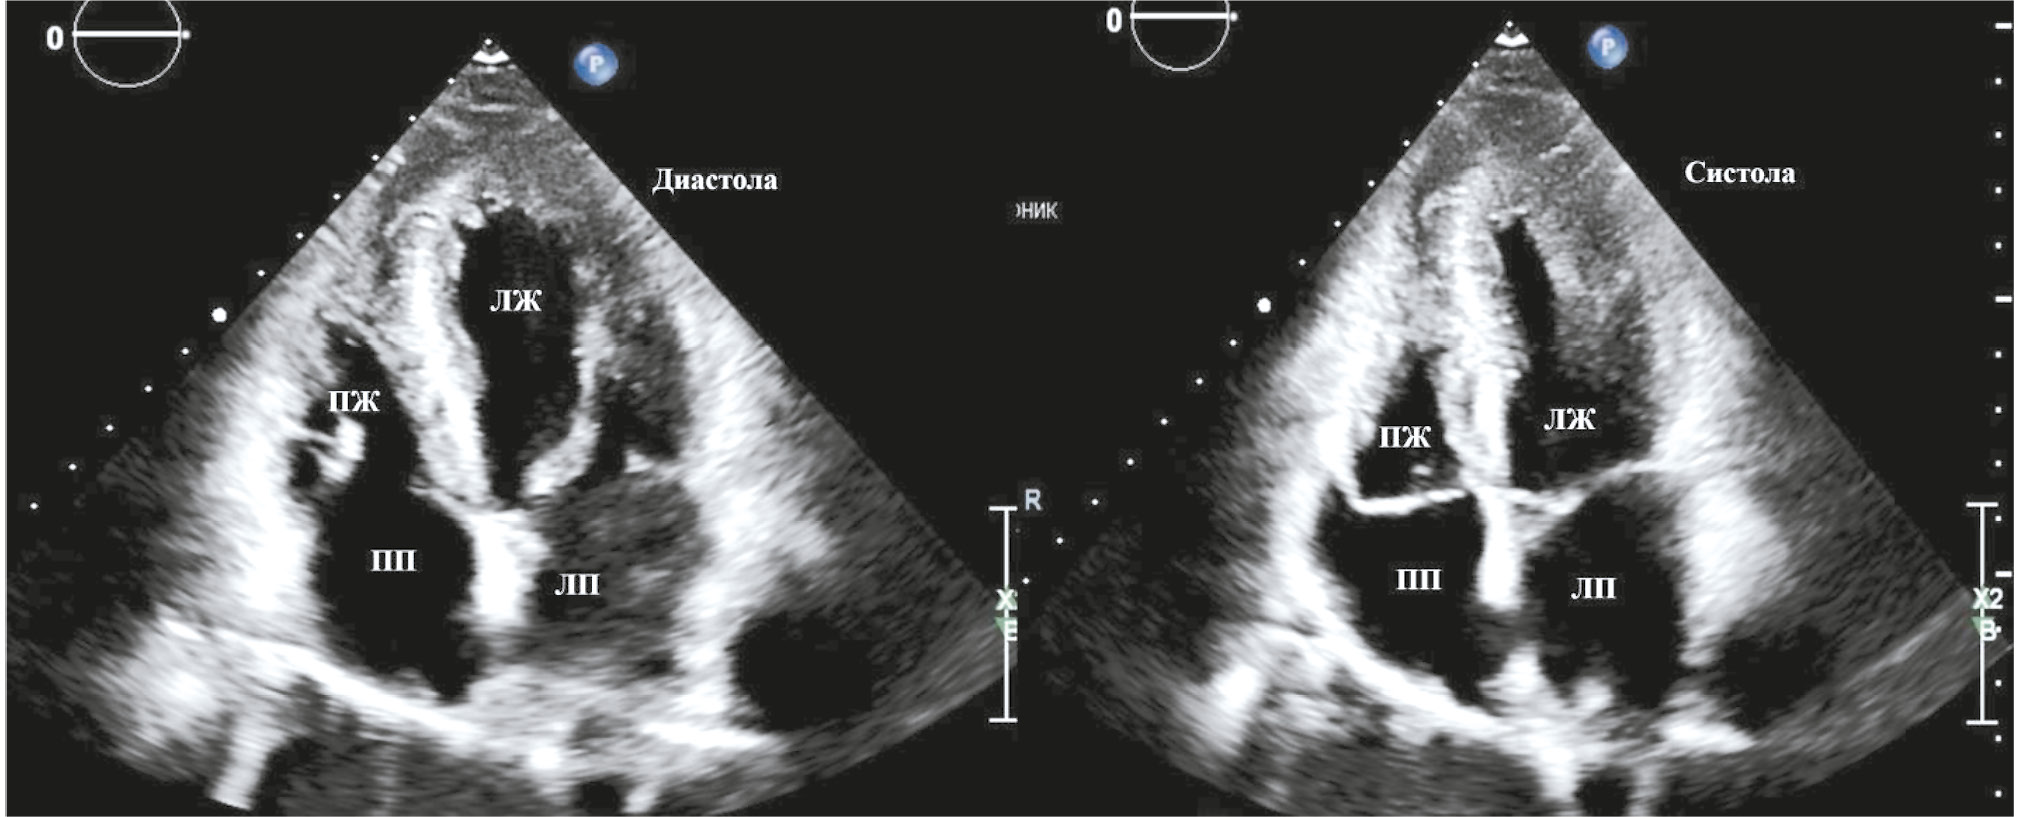

Рис. 5. Эхокардиография на десятые сутки госпитализации (слева — диастола левого желудочка, справа — систола).

Примечание. ЛЖ — левый желудочек, ЛП — левое предсердие, ПЖ — правый желудочек, ПП — правое предсердие.

Fig. 5. Echocardiography on the 10th day of hospitalization (left — left ventricular diastole, right — systole).

Note. ЛЖ — left ventricle, ЛП — left atrium, ПЖ — right ventricle, ПП — right atrium.

В отделении кардиологии пациентка получала эналаприл 5 мг в сутки, бисопролол 2,5 мг в сутки, амлодипин 2,5 мг в сутки, спиронолактон 25 мг в сутки, аспирин+клопидогрел, аторвастатин 80 мг в сутки, омепразол 20 мг в сутки, также были выполнены дообследования. По данным ЭхоКГ в динамике от 12.02: ФВ ЛЖ 46%, толщина МЖП 14,5 мм, толщина ЗС ЛЖ 14,5 мм, ЛЖ асимметрично гипертрофирован, на фоне пробы Вальсальвы признаки динамической ОВТЛЖ с умеренным ростом градиентов (Vmax — 3,5 м/с, dPmax — 48 мм рт. ст.), акинезия всех верхушечных сегментов и срединного сегмента МЖП. При этом при выполнении третьего ЭхоКГ-исследования на десятые сутки госпитализации (рис. 5–7) зон нарушения локальной сократимости выявлено не было, ФВ ЛЖ выросла до 61%, глобальная деформация ЛЖ снижена до -16%, МЖП — 15 мм, ЗС ЛЖ — 13–15 мм, передне-систолического движения створки митрального клапана не отмечалось, так же как и признаков ОВТЛЖ.